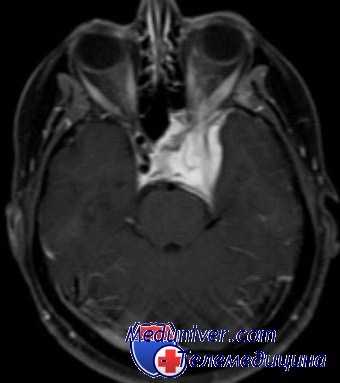

Прогрессивная рецидивная менингиома с обрастанием левого зрительного нерва.

Медленное прогрессирование в конечном итоге привело к потере зрения в левом глазу.

Было проведено радиохирургическое лечение. Менингиома краниовертебрального перехода, которую можно удалить без осложнений.